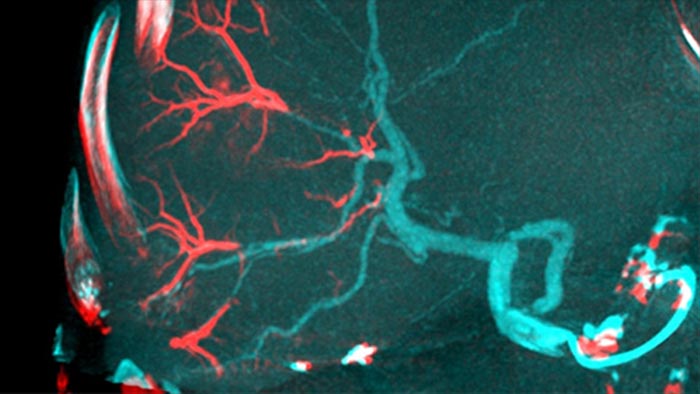

Al abrir el arco a la izquierda del paciente, CBCT Open permite el posicionamiento fuera del centro de la mesa del paciente y, por lo tanto, un mejor centrado del FOV3-4.Esto aumenta significativamente la cobertura de imágenes para ayudar a visualizar los tumores en la periferia del hígado.4.

Una adquisición 3D posterior a la embolización le permite visualizar la deposición dirigida de material embólico, como Liopidol o perlas radiopacas, en el tumor.5.